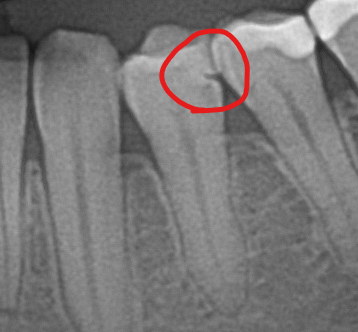

파노라마 사진에서 치아에 금같은것이 보이는데 괜찮을까요?

빨간 동그라미 친곳에 파인곳이 있는데 무엇일까요?

18~20개월 전에 치료받은 곳인데 깨진것으로 보이나요

사진처럼 보이는건 금간건 아니고 충치가 잇을것같습니다. 치과에 가셔서 재검진을 받아보시는게 좋을것같습니다.

레진이나 인레이 등으로 치료를 받으면 접착제로 인한 틈이 보이는 경우도 간혹 있어 사진만으로는 판별이 어렵습니다.

치료한 부위에서 치료한 재료와 자연치와에 사이에 틈이 있는 것으로 보이거나 아니면 x-ray에서 음영의 차이로 보이는 것일 수 있습니다. 찍는 각도에 따라 틈이 다르게 보일 수 있습니다. 치과에서 상의하는 것이 좋습니다.

사진으로 봤을 경우에는 충전한 충전 물과 치아 사이에 경계면에 틈이 있는 것으로 보입니다 이런 경우 경계 부위에 이물질이 들어가게 되어 축제 등이 생길 수 있습니다 원한다면 치료를 다시 해 보는 것도 좋은 방법이 될 수 있습니다 자세한 확인을 위해서 치과에서 진료를 받아 보세요